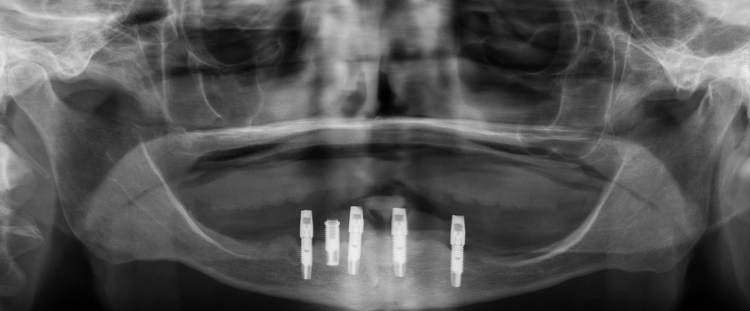

Fig. 19: Panoramic radiograph of the abutments seated on the four selected implants. Because the restoration is fully implant-supported, gradual diminution of the residual ridge will present no consequence to the patient.

A 73-year-old woman with a history of 11 years of complete edentulism of the maxilla and mandible, and five endosseous implants in the anterior mandible, presented with a chief complaint of a non-retentive and unstable lower denture. The implants were standard diameter, externally hexed, Brånemark fixtures. She had moderate resorption of both the maxillary and mandibular residual ridges (Fig. 1).

The patient had bone loss involving the implant bodies but comparing the radiographic evidence available, documenting her condition through the years, it appears the bone loss occurred soon after implant placement and no appreciable change was seen thereafter.

This copy serves as a temporary device for the patient to wear when cleaning the finished bridge or when sleeping to protect the tongue from scraping against the abutments. A panoramic radiograph was taken at completion of treatment (Fig. 19).